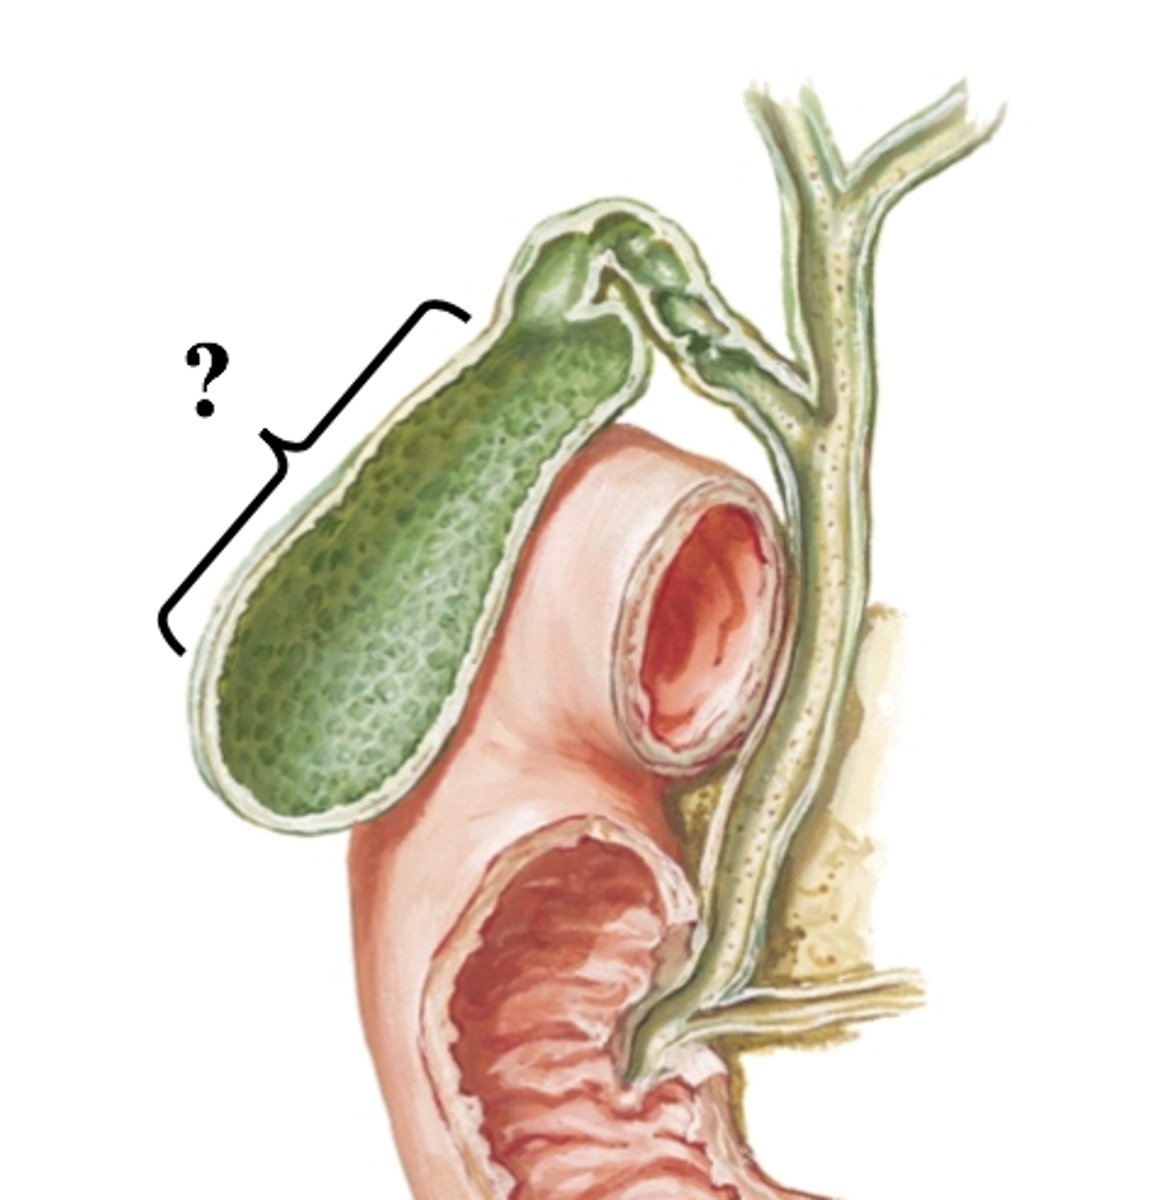

gallbladder

fundus (gallbladder)

body (gallbladder)

neck (gallbladder)

common bile duct

common hepatic duct

cystic duct